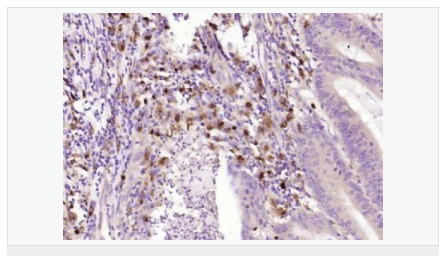

交叉反應:Human,Mouse,Rat(predicted:Pig,Horse,Rabbit) 推薦應用:WB,IHC-P,IHC-F,ICC,IF,ELISA

產品應用WB=1:500-2000 ELISA=1:5000-10000 IHC-P=1:100-500 IHC-F=1:100-500 ICC=1:100-500 IF=1:100-500 (石蠟切片需做抗原修復)